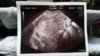

Super [emoji2] zdjęcie masz?Testy robiłam jakieś dwa dni temu powiem szczerze że już 4 dni przed planowaną miesiączką wyszedł pozytywny test . Zrobiłam ich w przeciągu 6 dni chyba ze 5tak bardzo uwierzyć nie mogłam . Wczoraj byłam u ginekologa ze względu na wcześniejsze nieprzyjemności i pracę fizyczną jaką wykonuję (praca na magazynie) i widziałam na USG mały pęcherzyk już